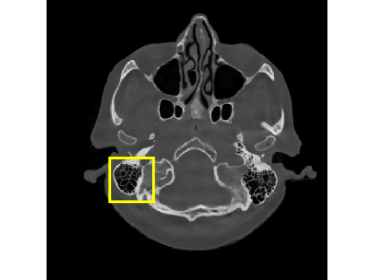

Finally, we apply the proposed method on a clinical head dataset. The data are acquired with a Siemens Artis zee angiographic C-arm system (Siemens Healthcare GmbH, Forchheim, Germany). In this experiment, we choose one slice of a 3D clinical head dataset as the ground truth image (Fig.9) and reproject it to simulate the acquired sinogram data in the fan-beam system with the following trajectory parameters: the source-to-isocenter distance is 750 mm and isocenter-to-detector distance is 450 mm. The angular step is 1 degree and the total scan range is 360 degrees. The equal-spaced detector length is 620 mm with the pixel length 111 mm.

The full projections are shown in Fig.10. When the detection range κ𝜅\kappa is limited, there could be saturation for the projection. In Fig.10 and Fig.10, observations for κ=0.6pmax𝜅0.6subscript𝑝\kappa=0.6p_{\max} and κ=0.4pmax𝜅0.4subscript𝑝\kappa=0.4p_{\max} are displayed, respectively. Our task is to recover the image from the saturated projections via M1bit-CS-ISD. The results are compared with FBP and SART, two standard CT reconduction frameworks. For FBP, we apply the modification given by [38] that utilizes water cylinder extrapolation to remedy missing projections caused by truncation or overexposure. For SART, one can remove those saturated projections when they are found, for which the ISD can be used as well. We denote this method as SART-ISD, of which the detection scheme is as the same as M1bit-CSR-ISD but SART is used as the reconstruction method.

For κ=0.6pmax𝜅0.6subscript𝑝\kappa=0.6p_{\max}, the reconstruction results of FBP-WCE and SART-ISD are given in Fig.9 and 9, respectively. As shown before, the traditional FBP method cannot handle the saturated data. With water cylinder extrapolation, the reconstruction quality has been improved but loss of clear patient boundaries still happens. The overall performance of SART-ISD is slightly better than FBP-WCE but capping artifact can be identified at the object border. Further improvement is obtained using the proposed M1Bit-CSR-ISD to acquire information from the saturated data. As shown in Fig.9, most of outer boundaries are nicely restored and streaking artifacts are effectively eliminated.

When the detectable range is smaller such that κ=0.4pmax𝜅0.4subscript𝑝\kappa=0.4p_{\max}, saturation becomes worse. Then the performance of FBP and SART, even with water cylinder extrapolation and the ISD scheme, dramatically drops. In practice, this heavy saturation rarely happens and is out of the scope of FBP-WCE. But even with this heavy saturation, the proposed M1bit-CSR-ISD can output a good result. The reconstructed images and enlargements of a region are illustrated in Fig.12 and Fig.13, respectively. In this case, both FBP-WCE and SART-ISD fail to restore the clear outer boundaries of the patient, while M1bit-CSR-ISD is still able to achieve this in a more accurate manner. We further report the saturation detection result in Fig.14, from which one can observe that most of the saturations have been properly detected.

Figure 12: Reconstruction results for the clinical data (κ=0.4pmax𝜅0.4subscript𝑝\kappa=0.4p_{\max}): (a) ground truth (yellow rectangle is enlarged in Fig.13); (b) FBP-WCE; (c) SART-ISD; (d) M1bit-CSR-ISD.